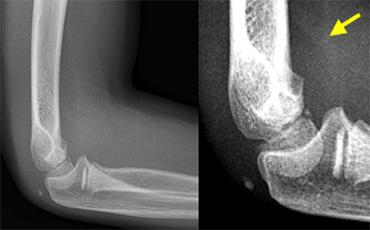

Dấu hiệu đệm mỡ dương tính

Sự căng phồng của khớp sẽ khiến đệm mỡ phía trước bị nâng lên và đệm mỡ phía sau trở nên hiện rõ.

Vùng thấu quang phía trước bị nâng cao hoặc vùng thấu quang phía sau hiện rõ trên phim X-quang thẳng nghiêm thực sự của khuỷu tay gấp 90° được mô tả là dấu hiệu đệm mỡ dương tính (hình).

Tràn máu khớp gây ra sự dịch chuyển lên trên của đệm mỡ trước và sự dịch chuyển ra sau của đệm mỡ sau.

Positive Anterior Fat Pad sign. On digital radiographs you may need to adjust the window width and level to appreciate this. No fracture was visible on the X-rays.

Dấu hiệu đệm mỡ dương tính (2)

Bất kỳ sự giãn khớp khuỷu nào do xuất huyết, viêm hoặc chấn thương đều tạo ra dấu hiệu đệm mỡ dương tính.

Nếu không có dấu hiệu đệm mỡ dương tính ở trẻ em, tổn thương trong khớp đáng kể là khó xảy ra.

Dấu hiệu đệm mỡ có thể nhìn thấy mà không phát hiện được gãy xương nên được coi là gãy xương ẩn.